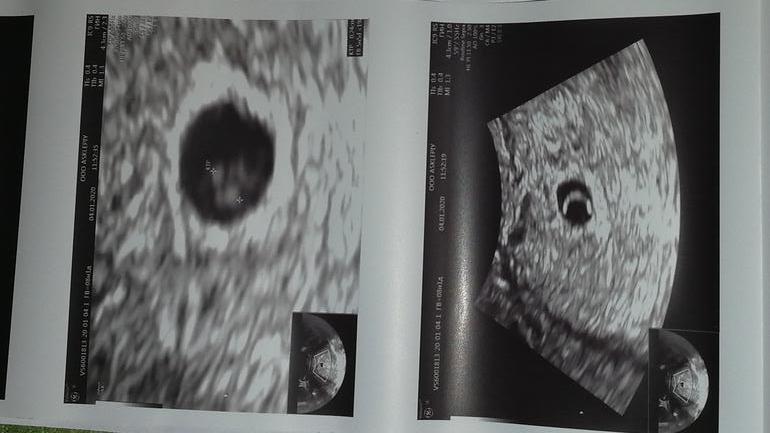

Ну не знаю, у кого там на таком сроке эмбрион находят, у меня в 5нед6дн нашли только плодное яйцо 94 мм и желточный мешочек. Ктр не замеряли даже.

Я вижу отчетливо эмбрион на снимке справа

Вот муж тоже видит, а я видимо насмотрелась вмдео где все красиво и понятно и тут ничего не разберу 😂Думаю наверное дотерпеть до 8 недели, это безумно сложно, но я постараюсь 😂

Вы поймите что аппарат узи это не микроскоп и у его разрешающей способности есть свой предел. Речь идет об эмбрионе размером 2.5 миллиметра!! Это не может быть человек с руками и ногами. Руки и ноги я увидела на узи в 8 недель. Сейчас он сам по себе похож на креветку но на узи и этого не видно потому что он слишком мал. Узист свою работу сделал хорошо, зря на него гоните, большинство на таком сроке не будут мерять эмбрион вообще. Напишут ЖМ+ и все.